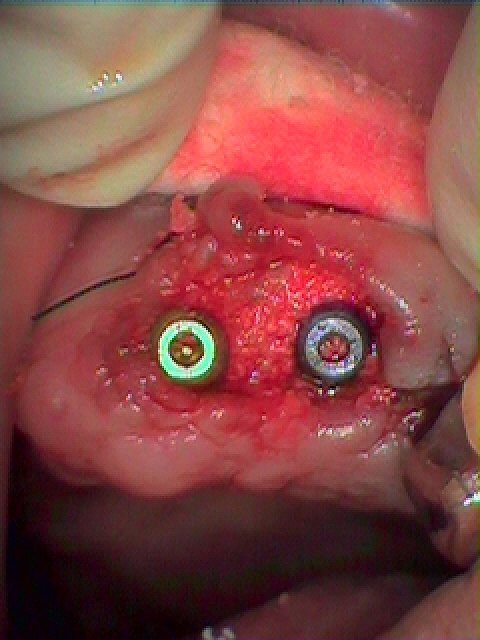

左上の2,3番部へ抜歯即時インプラント埋入を行っていきます|お知らせ |広島市安佐南区の歯科医院 左上の2,3番部へ抜歯即時インプラント埋入を行っていきます トップ お知らせ・ブログ お知らせ 左上の2,3番部へ抜歯即時インプラント埋入を行っていきます 左上の2,3番部へ抜歯即時インプラント埋入を行っていきます 術前の口腔内になります デンタルレントゲンになります インプラント埋入時になります インプラントが埋入 デンタルレントゲンになります 3か月待ちました 印象時になります カスタムのアバットメントから最終ジルコニアクラウンになります このように綺麗に入りました Web診療予約 初めての方へ 選ばれ続ける理由 院内設備について 歯が痛いしみる一般歯科 歯がぐらぐらする歯周病 健康な歯を保ちたい予防歯科 子供の虫歯予防をしたい小児歯科 銀歯をセラミックに審美歯科 白い歯を目指しませんか?ホワイトニング 矯正専門医がいるので安心矯正歯科 抜けた歯を補いたいインプラント・入れ歯 医院案内 スタッフ紹介 メリィハウス歯科クリニックオフィシャルホームページ ラベンダー歯科クリニックオフィシャルホームページ お知らせ・ブログ ホーム 診療科目 一般歯科 歯周病治療 予防治療 小児歯科 審美治療 ホワイトニング 矯正歯科 入れ歯・インプラント マウスピース矯正 初めての方へ 院長・スタッフ 設備紹介 医院案内・アクセス メニューを閉じる